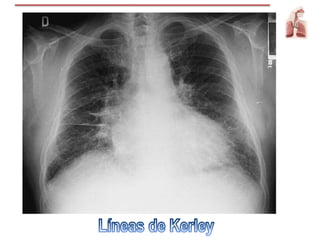

Radiografía de tórax

Bordes imprecisos

Imagen de mariposa

Cefalización

Líneas de Kerley

Oximetría / gasesarteriales Radiografía de tórax Bordes imprecisos Imagen de mariposa Cefalización Líneas de Kerley EKG / Ecocardiograma Lesión coronaria aguda Elevación de ST Aparición de onda Q significativa Hipertrofia ventrículo y/o atrio IZQ Marcadores de lesión cardiaca Cateterismo DER cardiaco